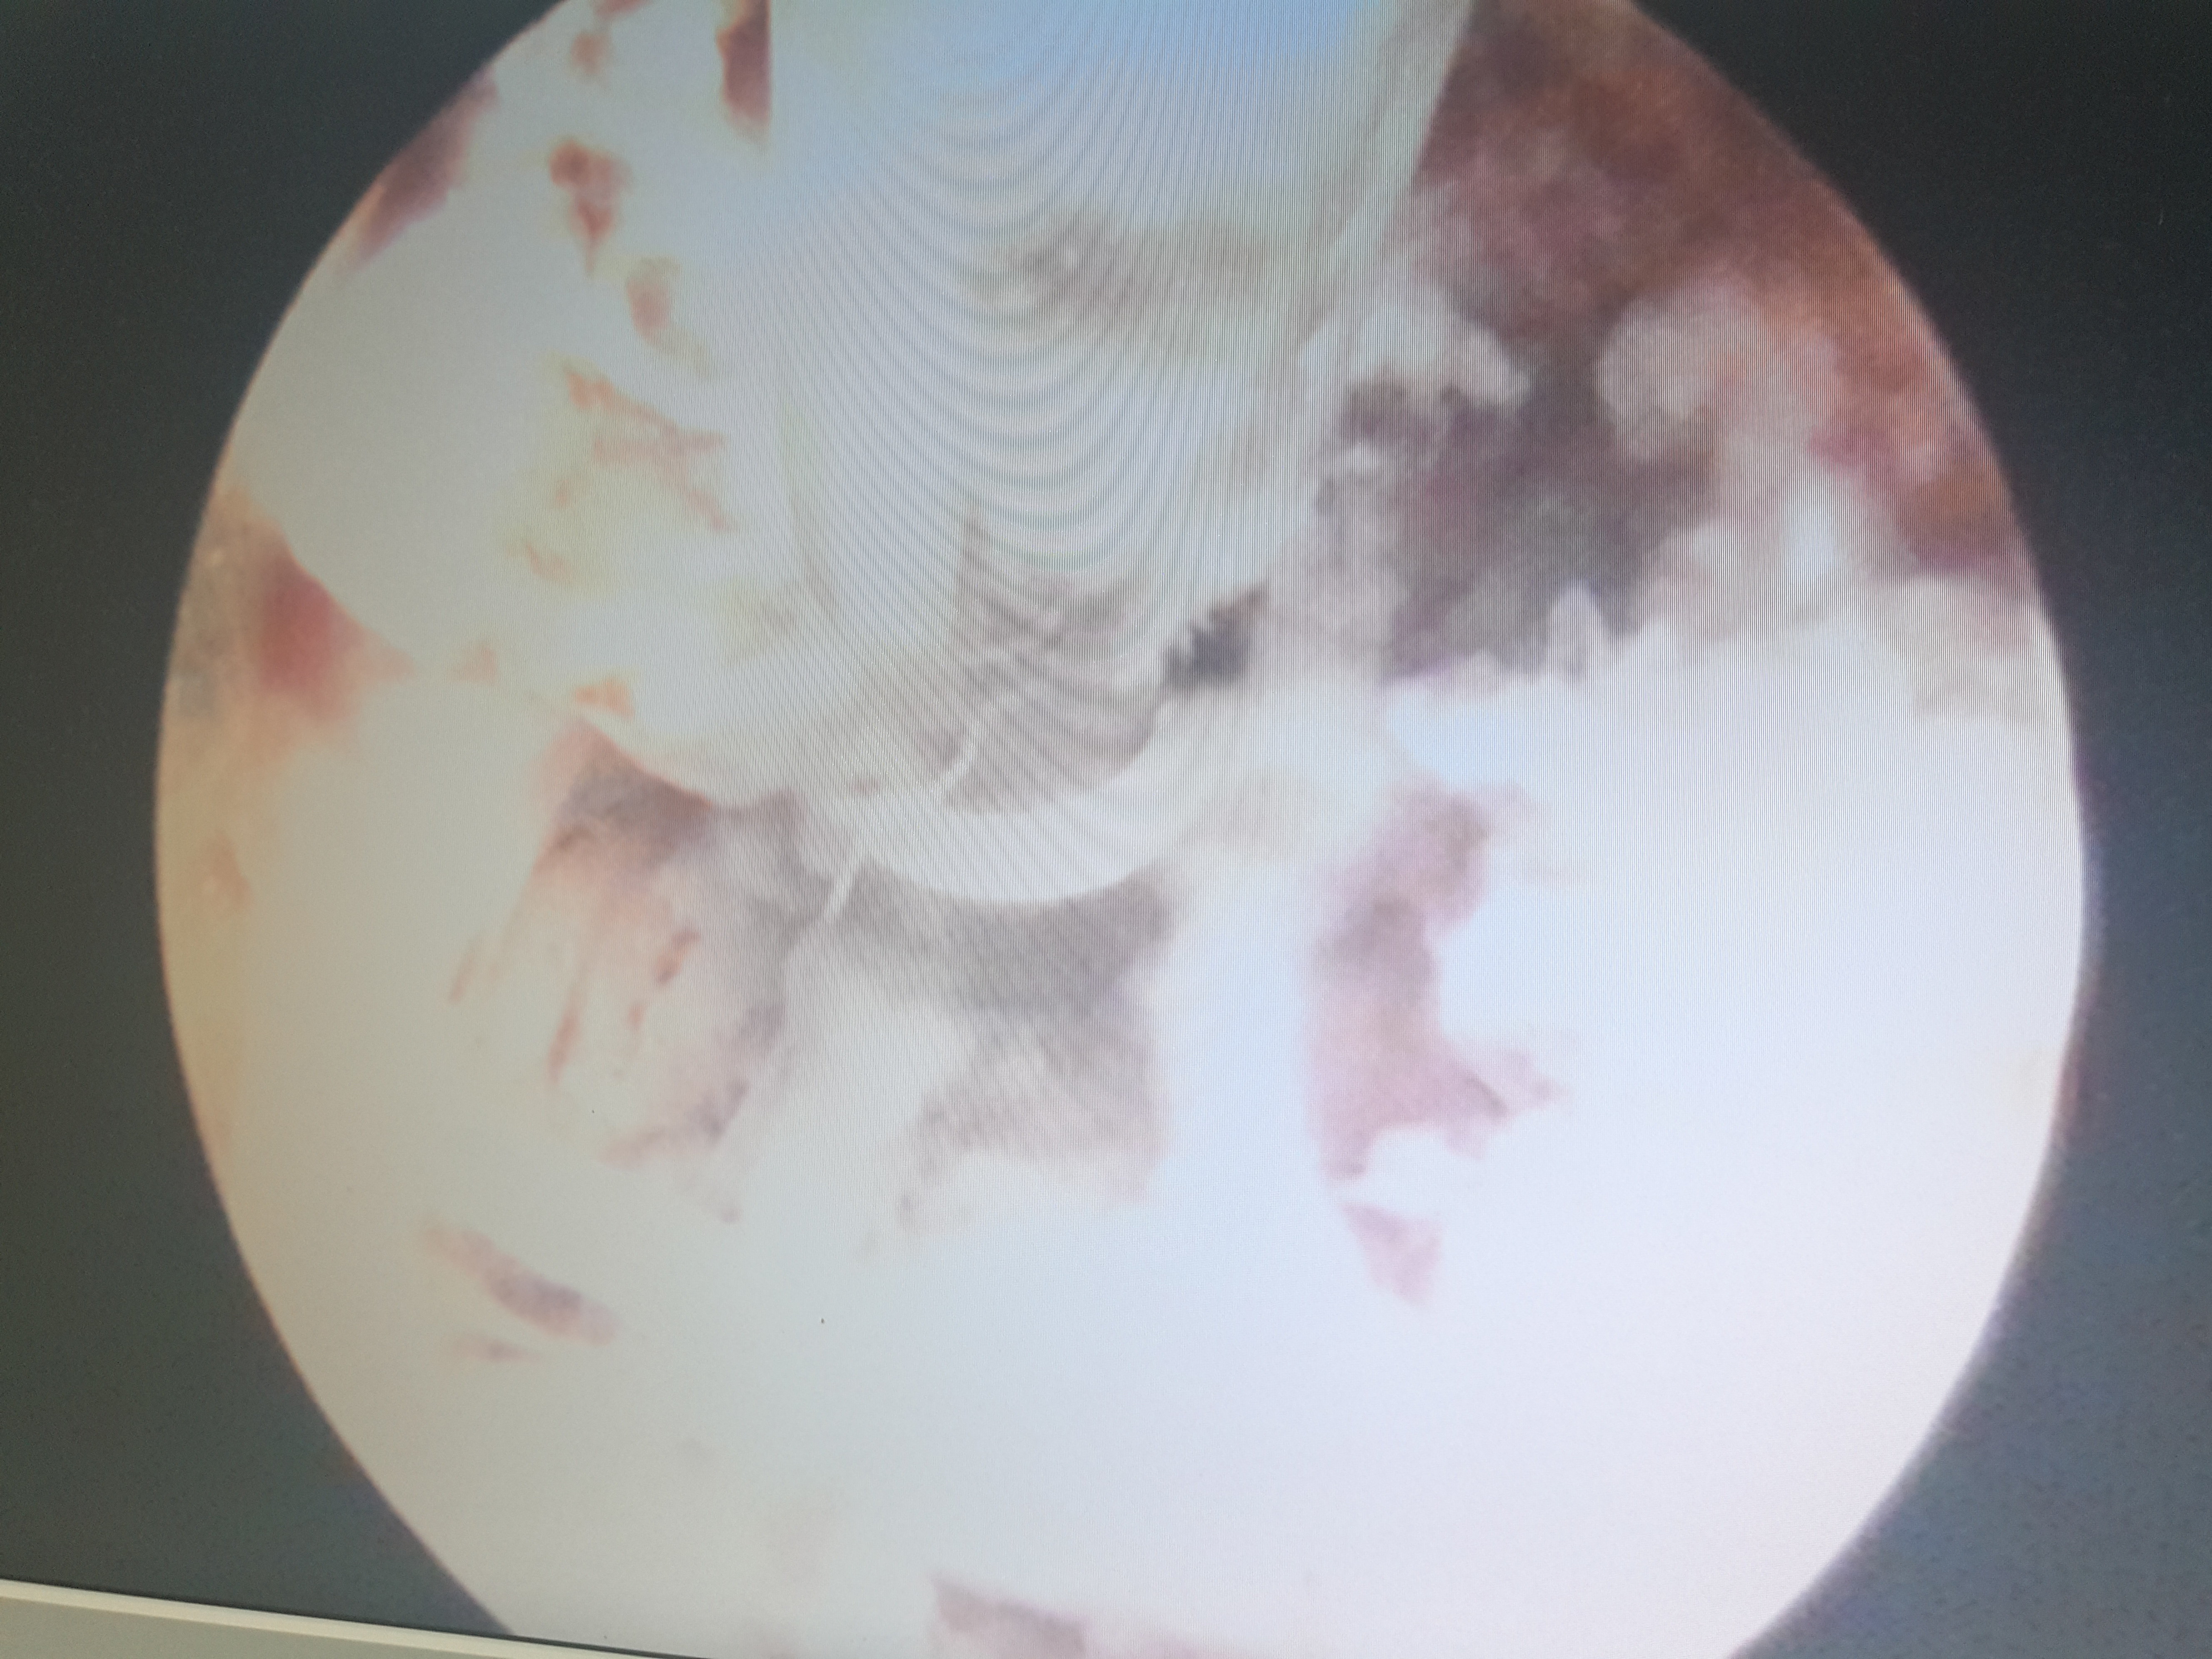

脊柱内镜翻修腰椎间盘突出症胶原酶溶核术后复

5312x3984 - 3474KB - JPEG

脊柱内镜翻修腰椎间盘突出症胶原酶溶核术后复

4340x3632 - 2061KB - JPEG